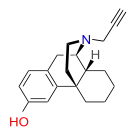

Morphinans

Morphinan series

- 3-Hydroxymorphinan

- 4-Chlorophenylpyridomorphinan

- Cyclorphan

- Levargorphan

- Levorphanol

- Levophenacylmorphan

- Levomethorphan

- Methorphan (racemethorphan)

- Morphanol (racemorphanol)

- Norlevorphanol

- N-Methylmorphinan

- Oxilorphan

- Phenomorphan

- Proxorphan

- Ro4-1539

- Stephodeline Xorphanol

Structures

| Other morphinans | ||||

|---|---|---|---|---|

4-chlorophenylpyridomorphinan 4-chlorophenylpyridomorphinan |

Cyclorphan Cyclorphan |

Dextrallorphan Dextrallorphan |

Levargorphan Levargorphan |

Levophenacylmorphan Levophenacylmorphan |

Levomethorphan Levomethorphan |

Norlevorphanol Norlevorphanol |

N-Methylmorphinan N-Methylmorphinan |

Oxilorphan Oxilorphan |

Phenomorphan Phenomorphan |

Dextromethorphan Dextromethorphan  levomethorphan levomethorphan |

Morphanol Morphanol |

Ro4-1539 Ro4-1539 |

Stephodeline Stephodeline |

Xorphanol Xorphanol |